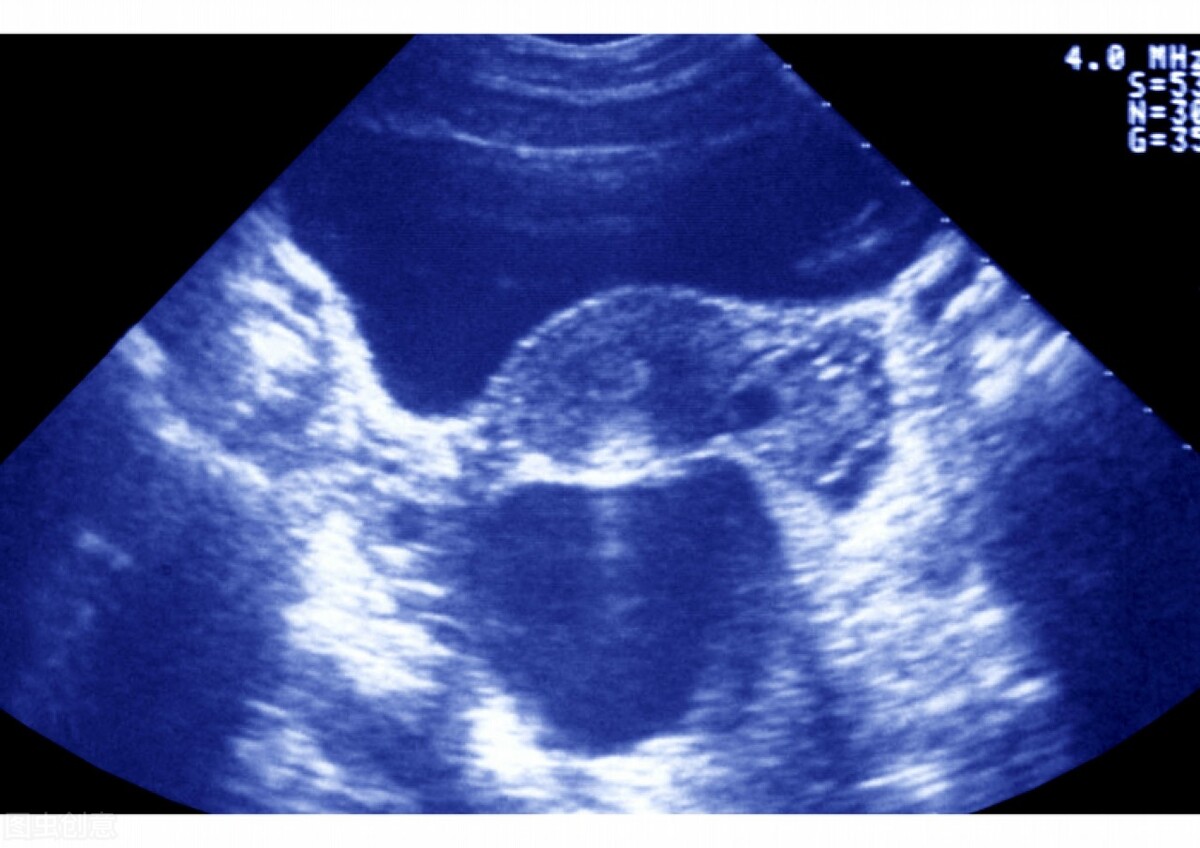

输卵管积水是输卵管炎症中较为常见的类型,在发生输卵管炎后,或者因为粘连闭锁,黏膜细胞分泌的液体堆积在管腔内,或者因输卵管炎症发生峡部以及伞端粘连,阻塞后形成输卵管积脓,当管腔内的脓细胞被吸收后,最终成为水样液体淤积。

关于输卵管积水的治疗主要有两种手段,如果暂时不要孩子的话可以采取保守治疗的方法——消除炎症,甚至可以在B超下将积水抽出,目的就是排出积水,减少对身体的伤害。如果有生育需求,那就通过微创手术的方法,通过伞端造口的方式疏通输卵管,积水自然就排出了。另外还有一种办法就是栓堵,将子宫与输卵管接口堵住,这样一来就不怕积水逆流了,但是弊端也很明显,就是这一侧的输卵管就不能使用了,只能靠另一侧抓卵受精,如果双侧都栓堵就只能做试管了。因为两个输卵管都被堵住,精卵一点见面的机会都没有,只能通过体外培育受精卵然后移植到体内的办法怀孕。